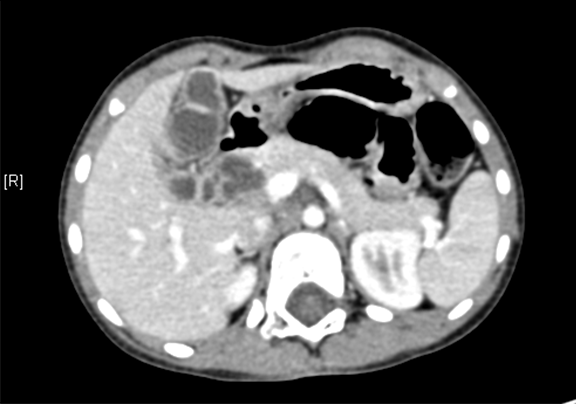

术前CT检查:

动脉期

静脉期

平衡期

将0.625mm双源薄层CT资料的静脉期和动脉期Dicom格式文件导入海信CAS系统。

通过调节窗宽窗位调整CT序号,对肝实质,胆囊,下腔静脉,肿瘤,肝动脉、门静脉及肝静脉等进行三维重建;系统自动计算肝脏体积。

术前手术方案的规划。